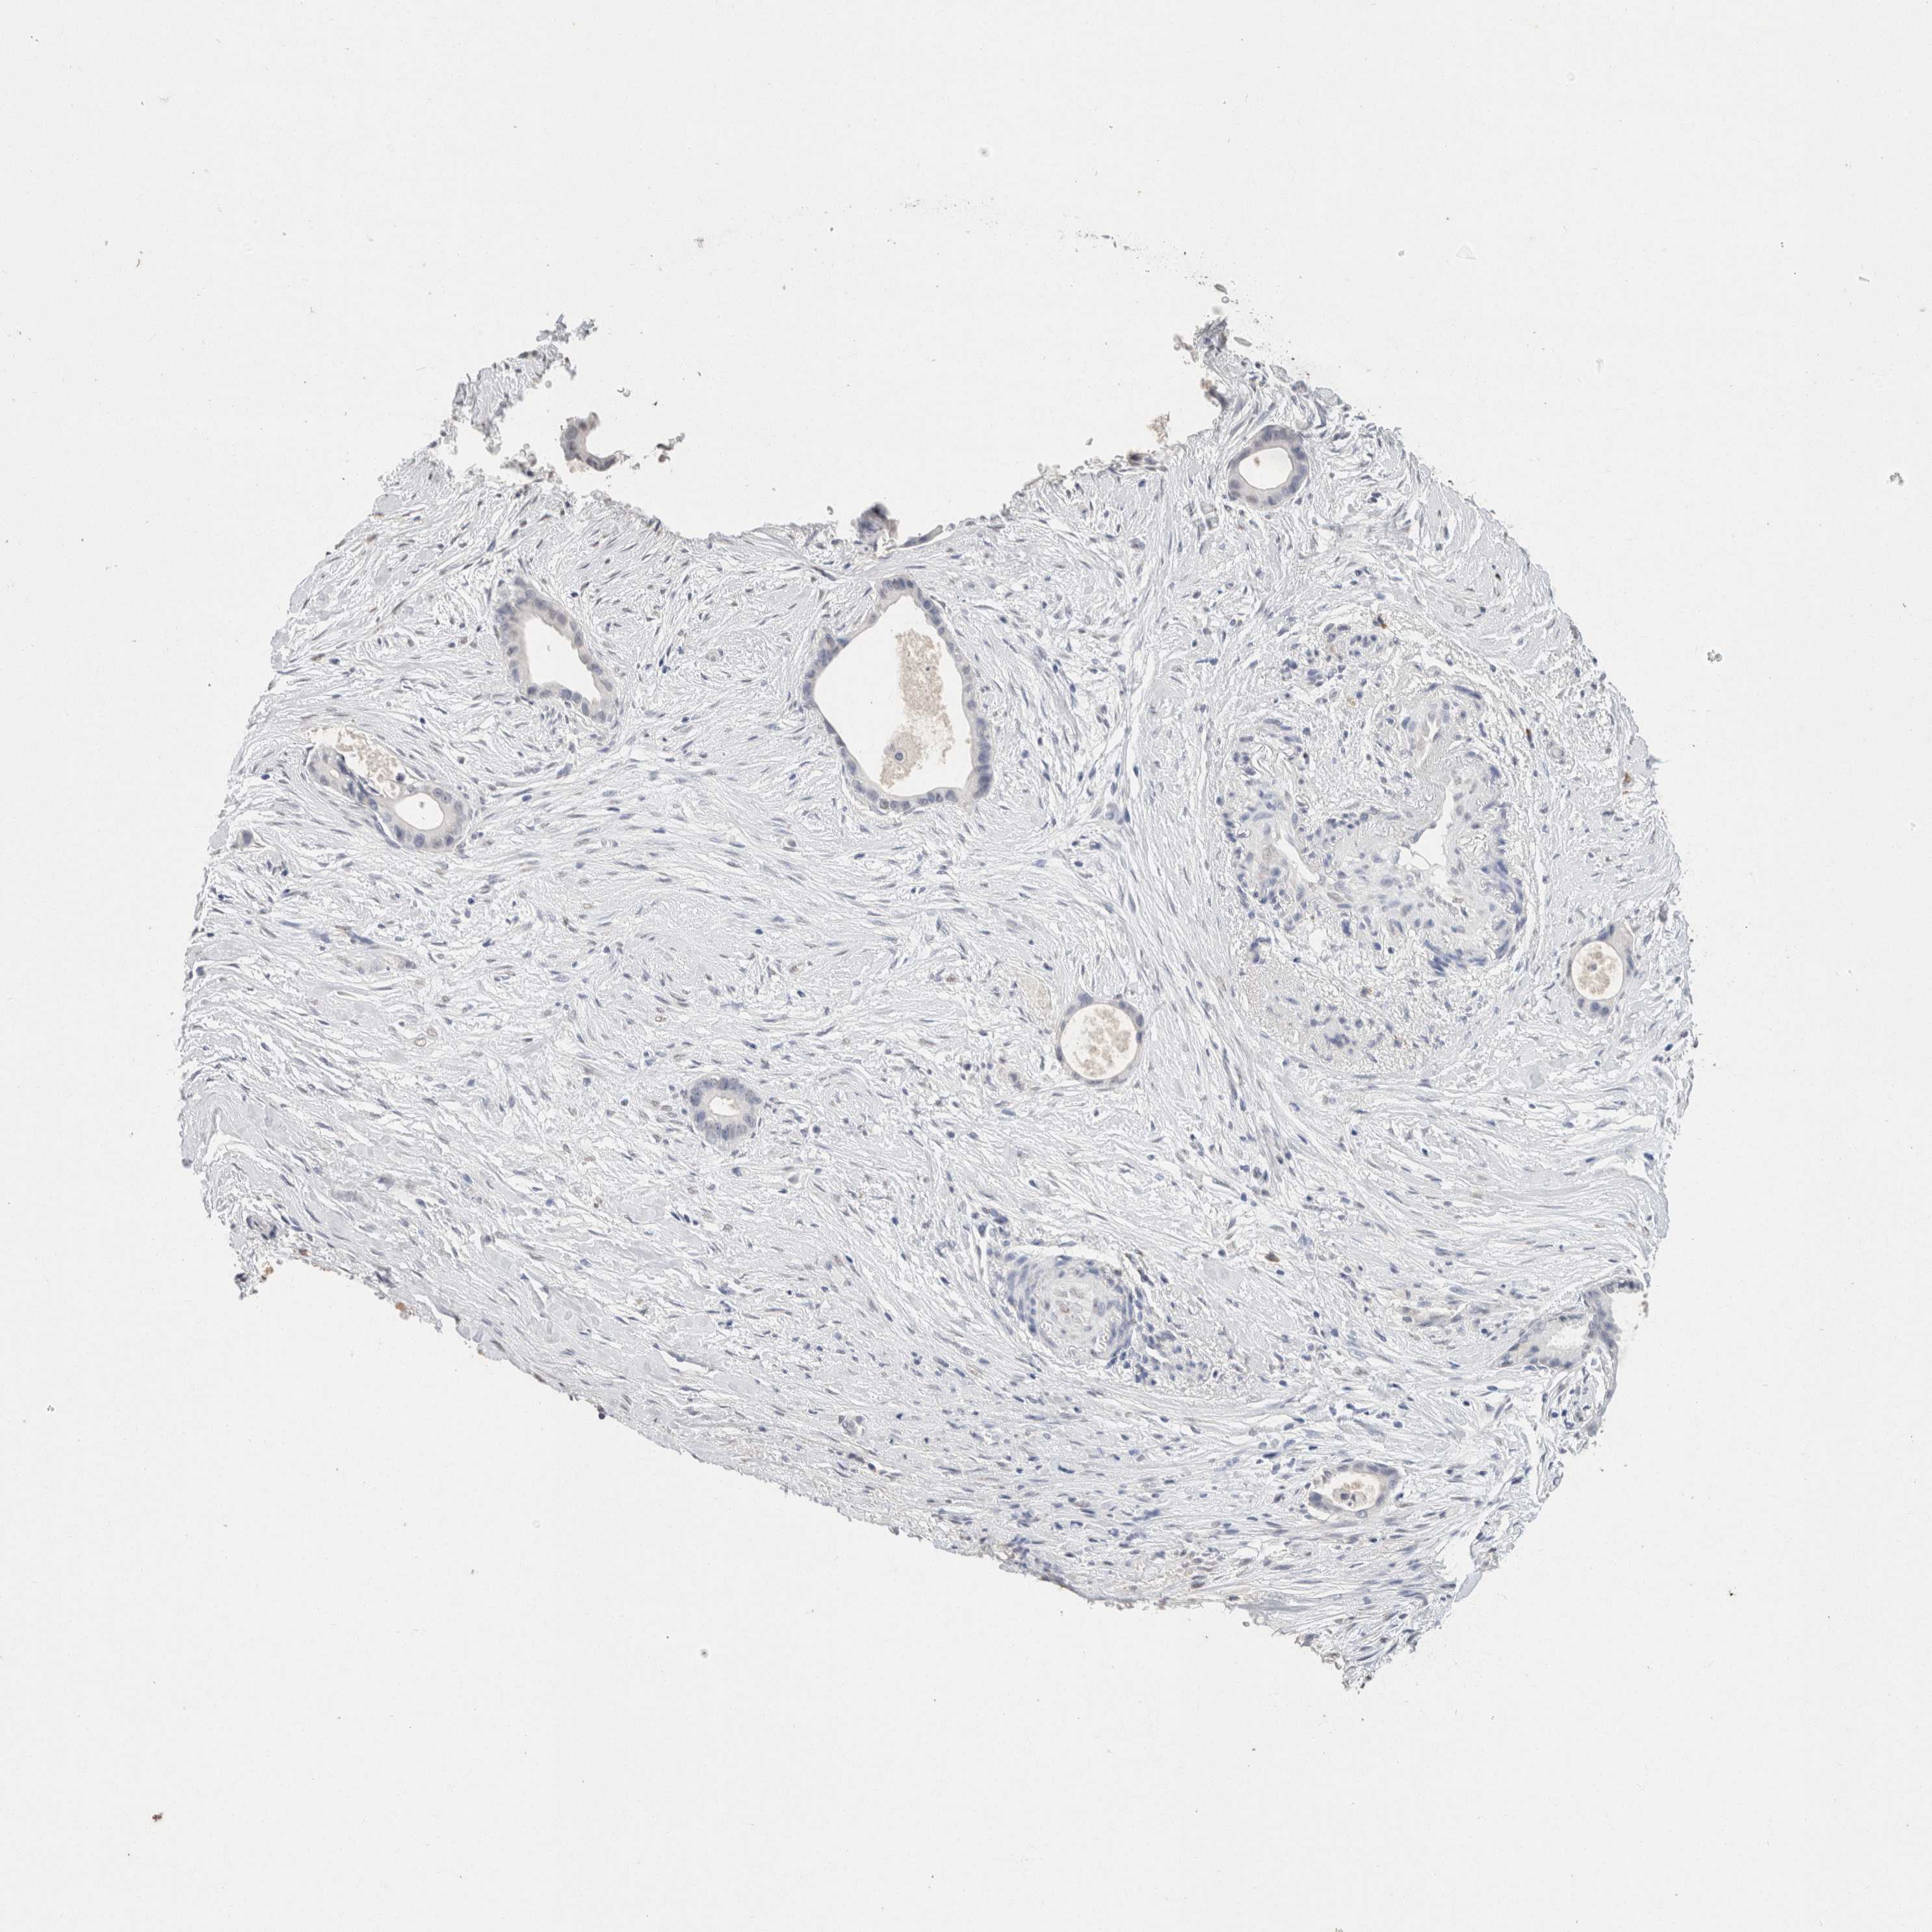

LIVER CANCER - Protein expressioni

A mouse-over function shows sample information and annotation data. Click on an image to view it in a full screen mode. Samples can be filtered based on level of antibody staining by selecting one or several of the following categories: high, medium, low and not detected. The assay and annotation is described here.

Note that samples used for immunohistochemistry by the Human Protein Atlas do not correspond to samples in the TCGA dataset.

Antibody stainingi

Antibody staining in the annotated cell types in the current human tissue is reported as not detected, low, medium, or high, based on conventional immunohistochemistry profiling in selected tissues. This score is based on the combination of the staining intensity and fraction of stained cells.

Each image is clickable and will lead to virtual microscopy that enables deeper exploration of all samples and also displays staining intensity scores, fraction scores and subcellular localization as well as patient and tissue information for each sample.

Antibody HPA050092

Antibody CAB025368

Staining

High

Medium

Low

Not detected

Intensity

Strong

Moderate

Weak

Negative

Quantity

>75%

75%-25%

<25%

None

Location

Nuclear

Cytoplasmic/membranous

Cytoplasmic/membranous,nuclear

Carcinoma, Hepatocellular, NOS

Cholangiocarcinoma